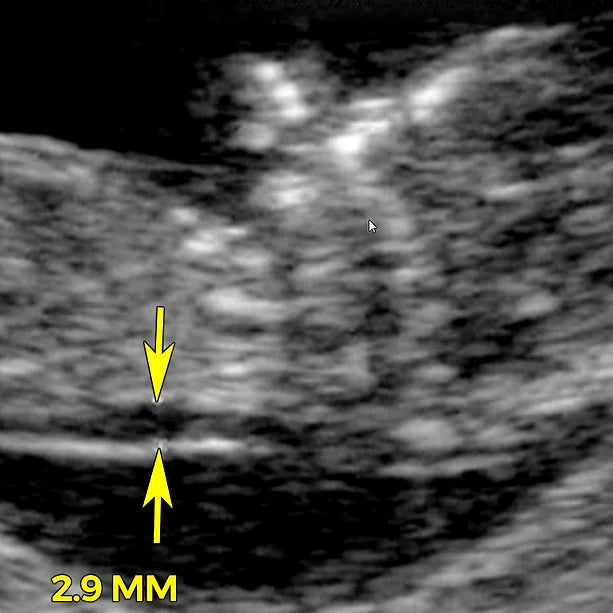

Nuchal translucency (NT) is a collection of fluid under the skin at the back of your baby's neck. The amount of fluid is measured during an NT ultrasound scan:

All developing babies have some fluid at the back of their neck. But many babies with Down syndrome or other chromosomal conditions have an increased amount. That’s why the NT scan is used to help screen for Down syndrome.

An NT ultrasound scan must take place between 11 weeks and 13 weeks plus six days, or when your baby’s crown rump length (CRL, the length from his head to bottom) is between 45mm and 84mm. It’s difficult to do the scan before 11 weeks because your baby is still so small. It’s too late to do the NT scan after 14 weeks, because any excess nuchal fluid may be absorbed by your baby's developing lymphatic system. The scan is usually done through your belly using normal ultrasound equipment. It shouldn't hurt, though you may feel some pressure as the sonographer presses the transducer into your skin to get a good view.